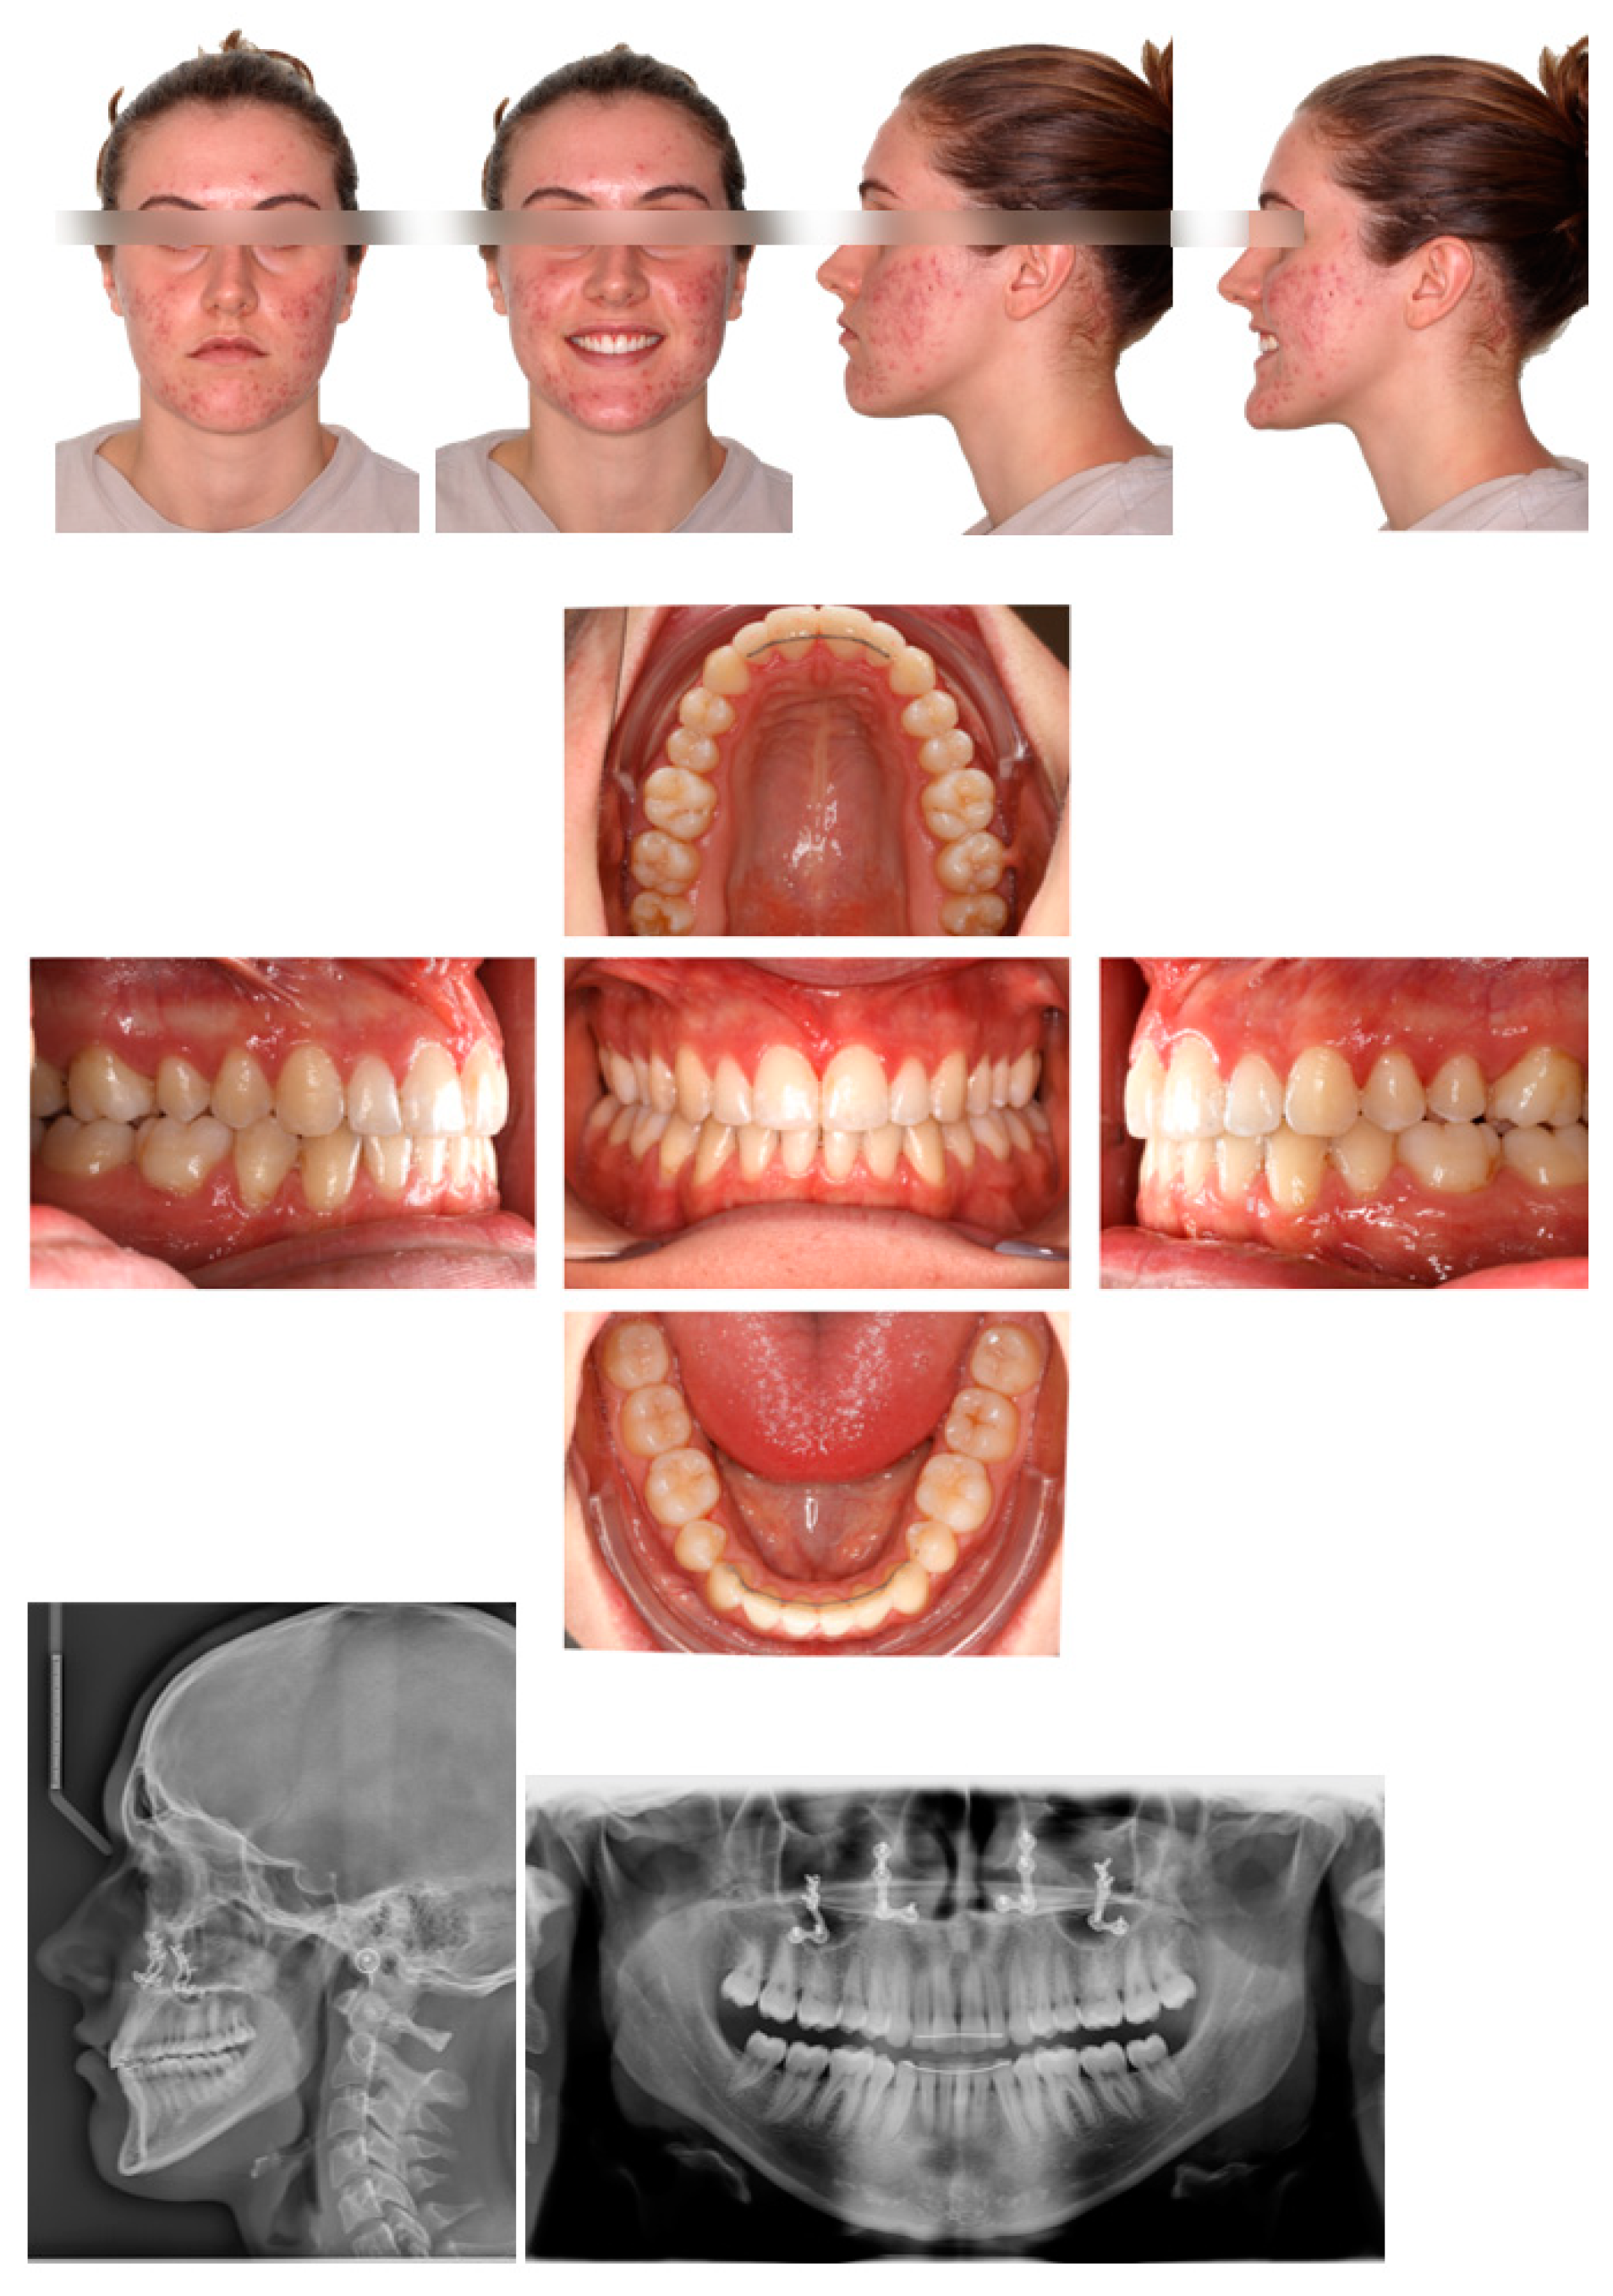

2.4. Post-Operative Orthodontic Phase